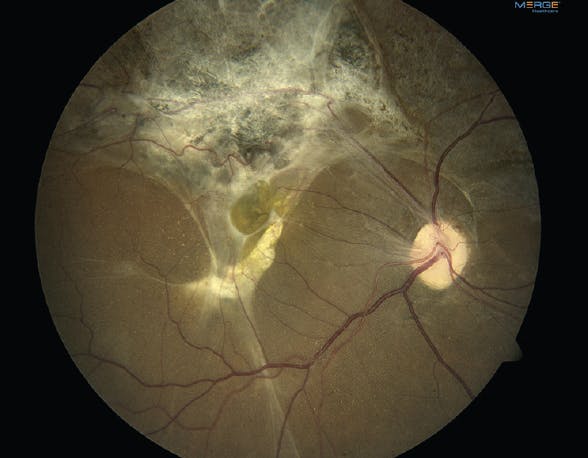

A 24-year-old man presented 3 months after multiple gunshot wounds to the head and orbit with VA of 20/150 OD and no light perception OS. There was a complete inoperable RD in the left eye, with the retina adherent to the posterior lens capsule. The anterior segment examination of the right eye was normal. The dilated fundus examination of the right eye revealed extensive scarring of the posterior pole with preretinal and subretinal membranes, consistent with a sclopetaria injury (Figure 2). OCT imaging of the right eye confirmed that the retina was detached at the macula (Figure 3). Due to concern for progressive loss of vision in this patient’s only seeing eye from the tractional RD, a 25-gauge vitrectomy with membrane peel was performed.

<p>Figure 3. The OCT of the right eye showed an RD at the macula.</p>

Figure 3. The OCT of the right eye showed an RD at the macula.

Because sclopetaria injuries are full-thickness ruptures of the retina and choroid, surgeons must remember that membranes can often traverse the entire thickness of the retina, and therefore they must peel judiciously. Careful assessment of the preoperative OCT can help demonstrate where the membranes span the retina and aid in surgical planning.